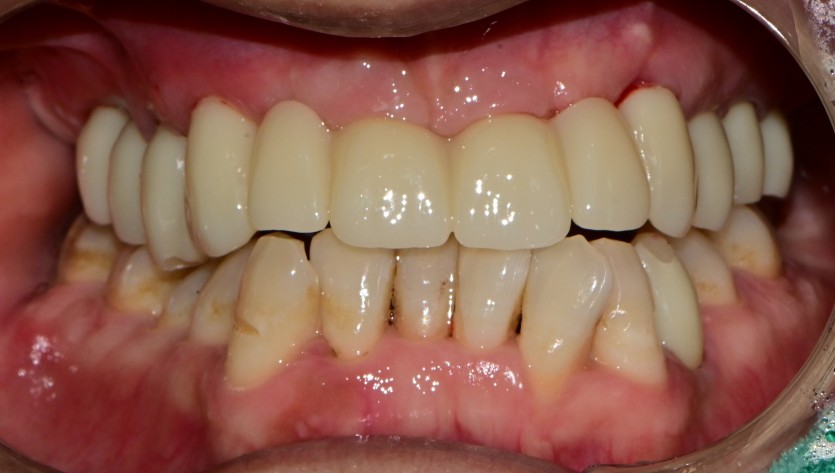

만 45세 상악 전체 임플란트 증례

상악 전체 임플란트 증례입니다.

10개의 임플란트로 완성하였습니다.